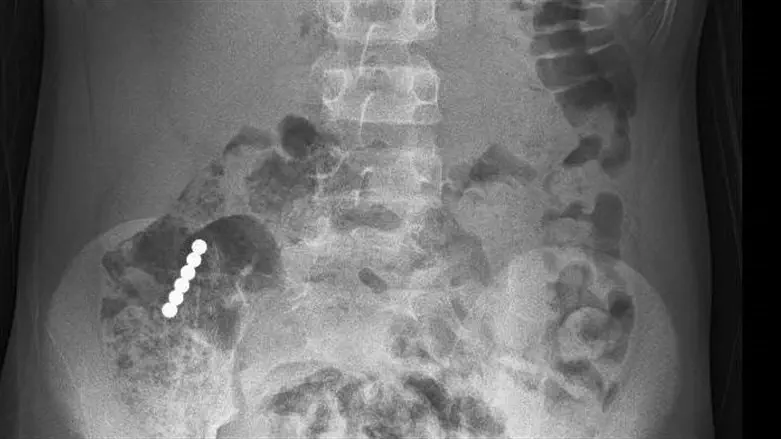

"במיון בוצע צילום שבו נצפו כל המגנטים באזור המעי הדק מעבר לקיבה, לכן לא בוצעה גסטרוסקופיה לשליפת הגופים הזרים. בשלב הראשון החלטנו לאשפז אותו להשגחה במחלקה כירורגית ילדים במטרה לאפשר למגנטים לצאת לבד ממערכת העיכול. המגנטים אכן התקדמו במערכת העיכול, אבל נתקעו בחיבור שבין המעי הדק למעי הגס. בתיאום עם הרופאים מכירורגית ילדים ובנוכחותם, הוחלט לבצע פעולת קולונוסקופיה תחת הרדמה מלאה במכון הגסטרו. בפעולה זו מוחדר צינור דק וגמיש שבקצהו יש מצלמה דרך פי הטבעת למעיים. הצלחתי לאתר את המגנטים ולשלוף אותם החוצה. בצעתי את הפעולה יחד עם אילנית לזימי, אחות אחראית יחידת גסטרו ילדים. המטופל התאושש במהירות ושוחרר כשהוא מרגיש טוב, ללא הקאות או כאבי בטן".